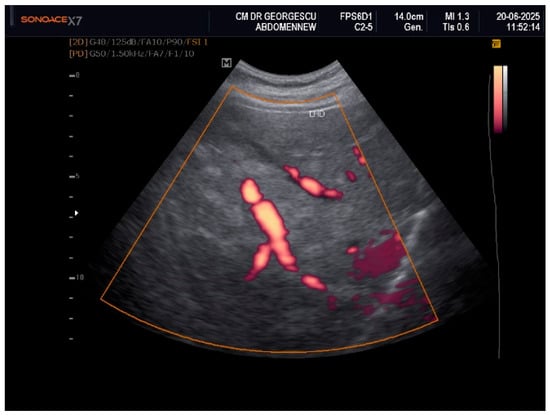

Liver Lipodystrophy in Barraquer–Simons Syndrome: How Much Should We Worry About?

Lipodystrophy is a rare group of metabolic disorders characterized by the abnormal distribution of body fat, which can lead to various metabolic complications due to the body’s inability to adequately process carbohydrates and fat. We report the case of a female, aged 53 years, who was admitted as an outpatient for progressive weight loss of the upper part of the body (face, neck, arms, and chest), dyspeptic complaints, fatigue, mild insomnia, and anxious behavior. Her medical history was characterized by the presence of dyslipidemia, hypertension, and a minor stroke episode. However, she denied any family-relevant medical history. Although the clinical perspective suggested a possible late onset of partial acquired lipodystrophy, due to the imaging exam that revealed an enlarged liver with inhomogeneous structure with multiple nodular lesions, scattered over both lobes, a lot of lab work-ups and complementary studies were performed. Eventually, a liver biopsy was performed by a laparoscopic approach during cholecystectomy, the histology consistent with metabolic disease-associated steatohepatitis (MASH). In conclusion, given their heterogeneity and rarity, lipodystrophies may be either overlooked or misdiagnosed for other entities. Barraquer–Simons syndrome (BSS) may be associated with liver disease, including cirrhosis and liver failure. Liver lipodystrophy in BSS may sometimes feature steatosis with a focal, multi-nodular aspect, multiplying the diagnostic burden. Liver lipodystrophy may manifest as asymptomatic fat accumulation but may progress to severe conditions, representing one of the major causes of mortality in BSS, apart from the cardio-vascular comorbidities. Given the potential of severe outcomes, it is mandatory to correctly assess the stage of liver disease since the first diagnosis. Full article

Figure 1